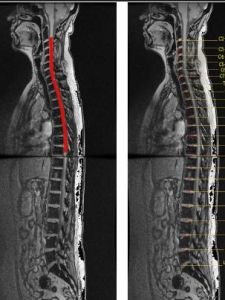

(2)間接外力交通事故,高處墜落及跳水意外時,外力多未直接作用於脊柱、脊髓,但間接外力可引起各種類型不同的脊柱骨折、脫位,導致脊髓損傷。間接外力作用是造成脊柱、脊髓損傷的主要原因。Gosolf等用猴進行多種活體脊柱損傷實驗,結論是要造成骨折脫位,除屈伸暴力外,必須要有軸向鏇轉暴力。而發生脊髓損傷的力的閾值,還受肌肉張力的重要影響。Gusta等報告46.3%的脊髓損傷患者是因剪力和扭力作用造成骨折脫位損傷脊髓,30.5%是因脊柱前中後三柱受壓損傷的結果,15.8%是因脊柱前中二柱受損結果,4.2%因過伸性脊柱損傷引起,而3.2%則是因外傷間盤突出引起脊髓損傷。近年來,人們注意到有些脊髓損傷並不伴有脊柱的骨折脫位,即外力的作用造成了脊髓損傷而沒有影象學可見的脊柱骨折脫位等異常發現。兒童的脊髓損傷多屬此種情況即SCIWORA。成人患者中有退化性脊椎病,椎管狹窄者也易發生,因易誤診應引起重視。MRI和電生理診查可為無骨折脫位的脊髓損傷提供一定診斷依據。了解外傷性脊髓損傷的具體原因,對採取相應措施預防或減少脊髓損傷的發生有重要意義。如高空作業安全帶的套用,汽車駕駛的安全帶的套用,嚴禁酒後開車以及最近汽車內防撞系統的套用等,均對脊髓損傷的預防有重要意義。